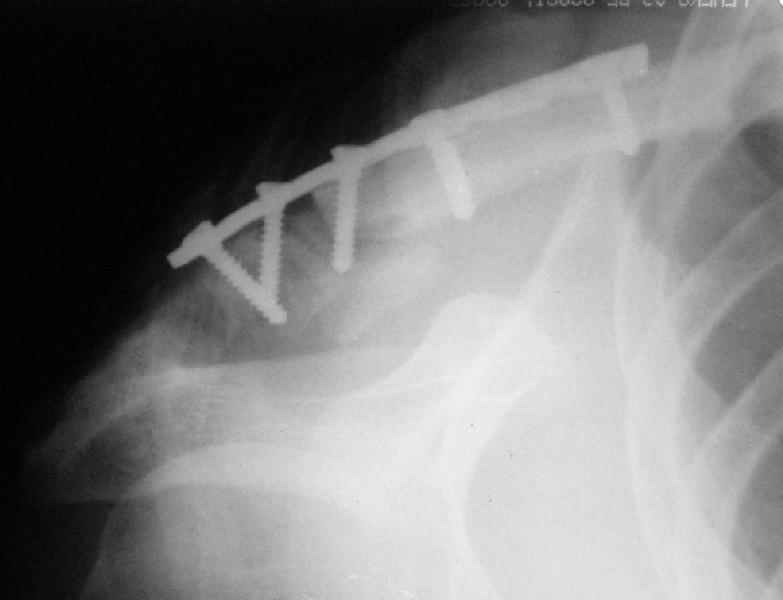

Сегодня прооперировал больного - накостный остеосинтез реконструктивной пластиной с ааллотендопластикой кл-кл связки.

На операции - обширная межотломковая ткань - мобилизовал проксимальный отломок без иссечения м-отломк.ткани, резекция выступающего конца( в последующем использовал как трансплантат).

Однако, я сомневаюсь в правильности выбора метода фиксации - фактически только 1 винт (на акромиальном отростке) является рабочим и мне кажется зря вы не убрали рубцы из зоны перелома - для костного сращения контакт кость-кость вроде бы как желателен.

Время покажет, не мигрировал бы только этот самый рабочий винт из губчатой кости....

После мобилизации проксимального отломка достигнут контакт в нижней части . 2 винта в дистальном отломке + петля аллосухожилия, проведенная через канал в проксимальном отломке должна нейтрализовать смещающие силы - надеюсь.